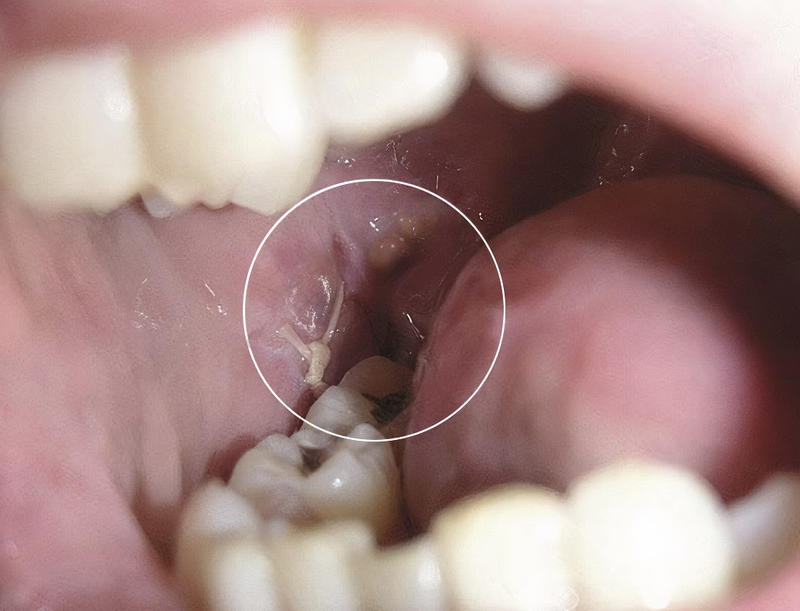

- Răng khôn mọc một phần: Khi răng chỉ nhú lên một phần qua nướu, giữa nướu và thân răng sẽ hình thành một khe nhỏ. Đây là nơi thức ăn và vi khuẩn dễ tích tụ, lâu ngày có thể gây viêm lợi trùm và nhiều biến chứng răng khôn khác.

- Viêm lợi trùm: Phần lợi phủ lên một phần thân răng khôn dễ tích tụ thức ăn và vi khuẩn. Khi vùng này bị viêm, nướu sẽ sưng đỏ, đau nhức và có thể gây khó há miệng hoặc khó nhai, đây là một dạng biến chứng răng khôn rất phổ biến.